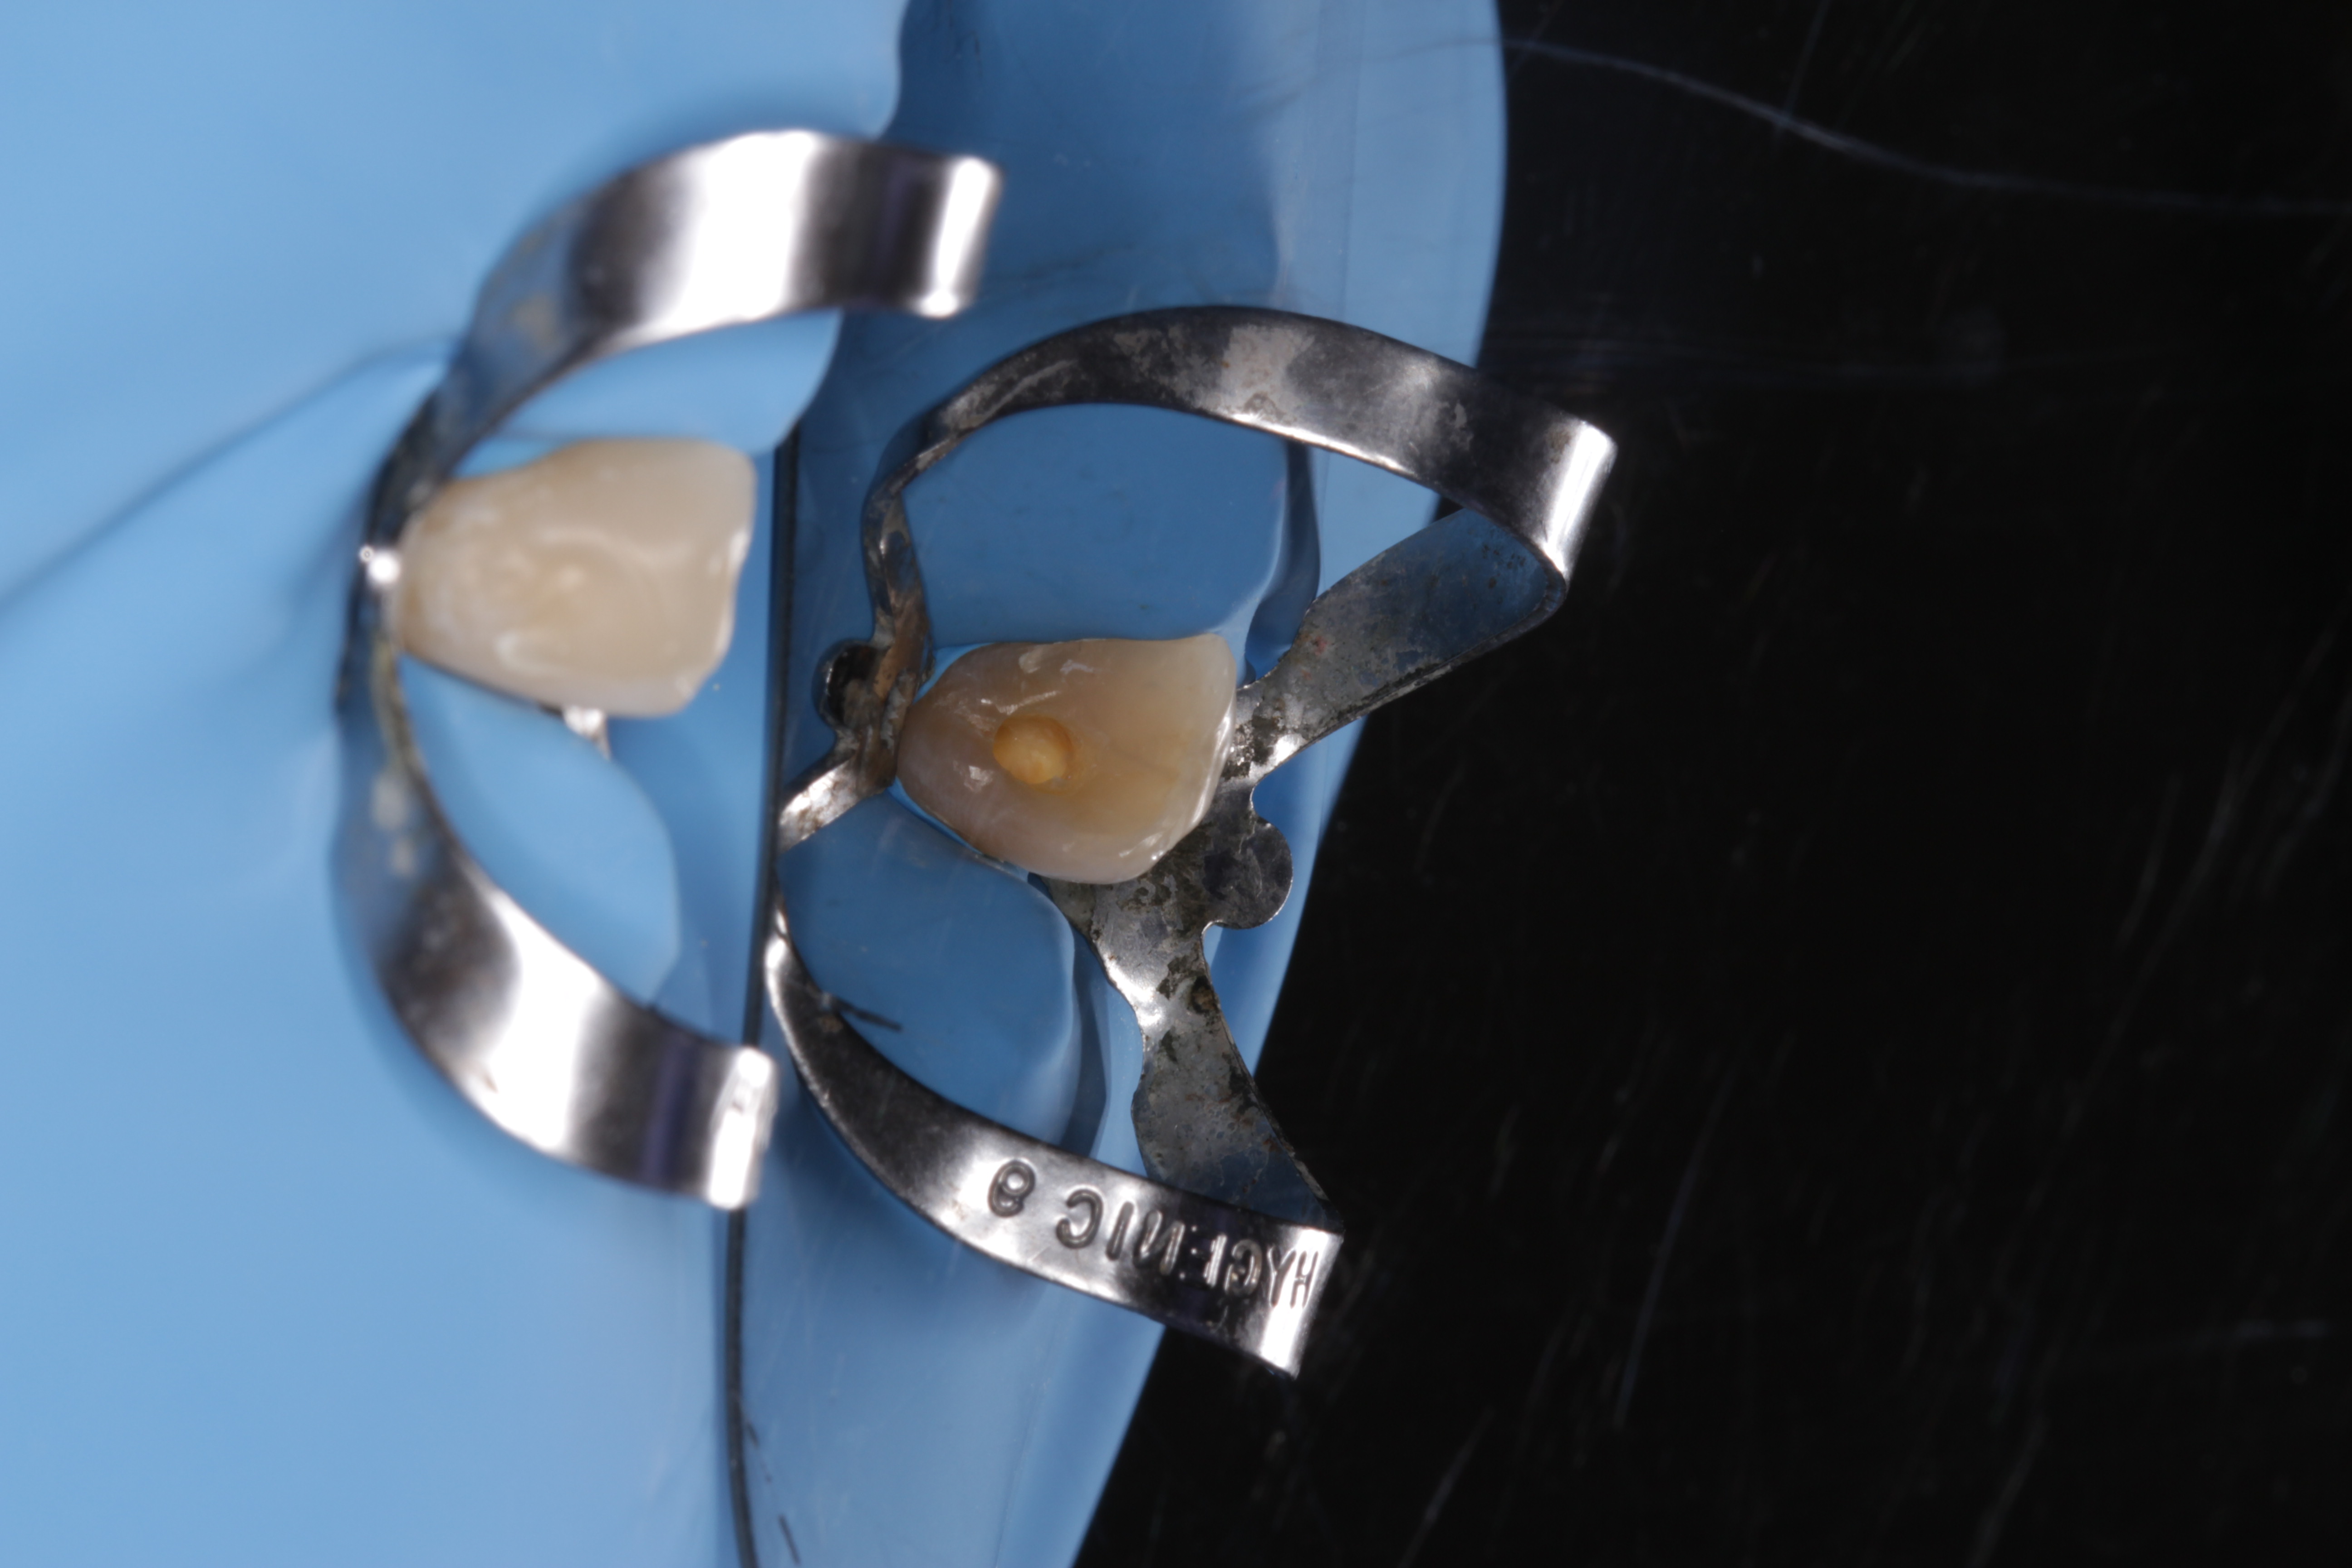

- Tratamiento

- Prótesis parcial acrílica

- Metal cromo-cobalto

- Técnica BOPT